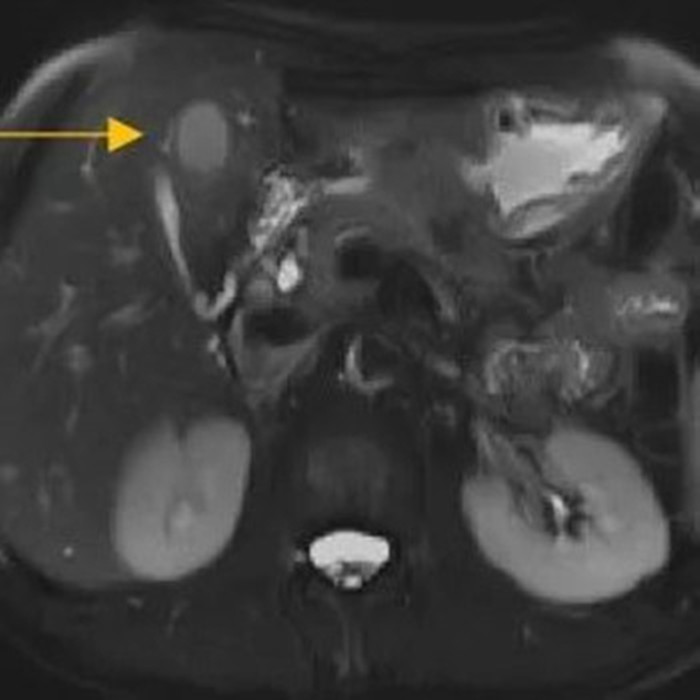

住院后經(jīng)胸腹部CT檢查,提示周先生胃部巨大腫塊穿破胃腔,可能累及到結(jié)腸,同時(shí)合并有胃旁淋巴結(jié)轉(zhuǎn)移、肝臟的轉(zhuǎn)移??吹竭@個(gè)檢查報(bào)告后,周先生和他的愛人一下子就泣不成聲了。

治療前的腹部CT提示胃

治療前肝臟的轉(zhuǎn)移灶

經(jīng)過6個(gè)周期,前后4個(gè)月的治療,周先生再次復(fù)查CT,提示胃部腫瘤,轉(zhuǎn)移的胃旁淋巴結(jié)、肝臟腫瘤都有明顯縮小,營養(yǎng)狀況良好,能正常進(jìn)食,體重增加了6斤,精神狀態(tài)比原先好了很多。